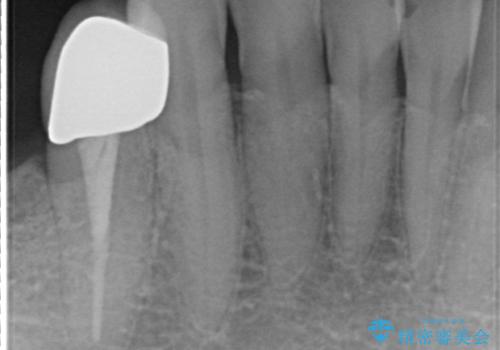

- 右下でものを咬むと痛むので診て欲しいといらっしゃった方の症例です。

右下6番目の歯を診査したところ歯根が破折していたため、保存不可能であることを説明し抜歯しました。

その後右下5、6番目にはインプラントを埋入し、右下3、4、5、6、7番の歯の補綴をオールセラミッククラウンによって行いました。